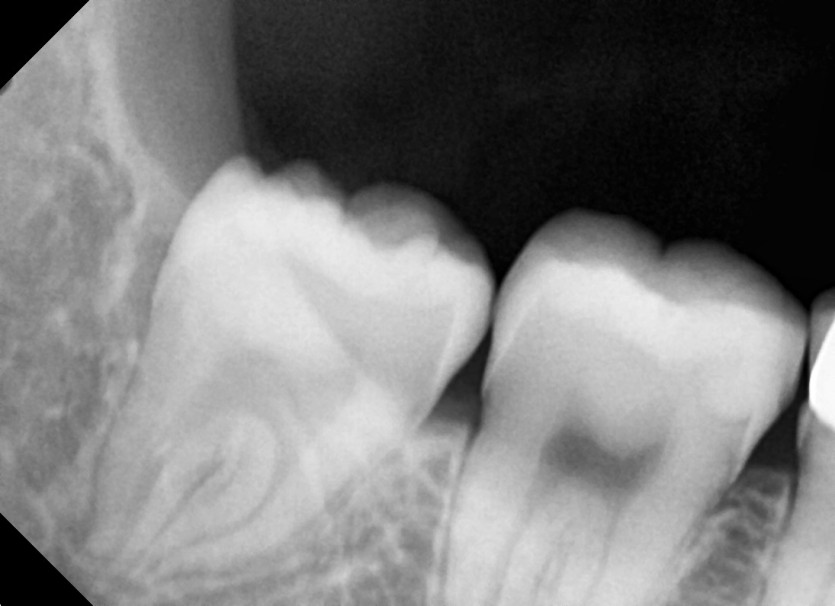

#18,48 사랑니 발치

구강 외과 전문의가 당일 발치했습니다.